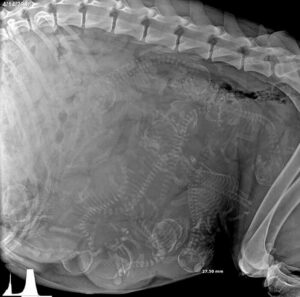

لا تقلق، فهذا طبيعي تماما

في غياب عنوان محدد يشرح ماهية هذه الصورة، قد يضطر عقلك لبذل كل جهده بغية التوصل إلى احتمالات تشرح المظهر

الغريب الذي شكله عدد لا يحصى من الهياكل العظمية الصغيرة داخل جسم واحد. لكن بمجرد أن تفهم ما يجري هنا يصير

السياق مفهوما، إلى حد ما. إنها مجموعة من الجماجم والعظام التي تتكدس معا في مكان ضيق، ومن المخيف أن يكون هذا

كله أمرا طبيعيا تماما. انظر جيدا: إنها مجموعة من الجراء الصغيرة التي ستأتي إلى هذا العالم عما قريب!

رغم أن الناس معتادين على رؤية الصور الضوئية الملتقطة عبر الموجات فوق الصوتية للحمل، إلا أن هذه الأشعة السينية لبطن كلبة حامل تؤكد لنا في بعض الأحيان أنها صادمة إلى أبعد حد.